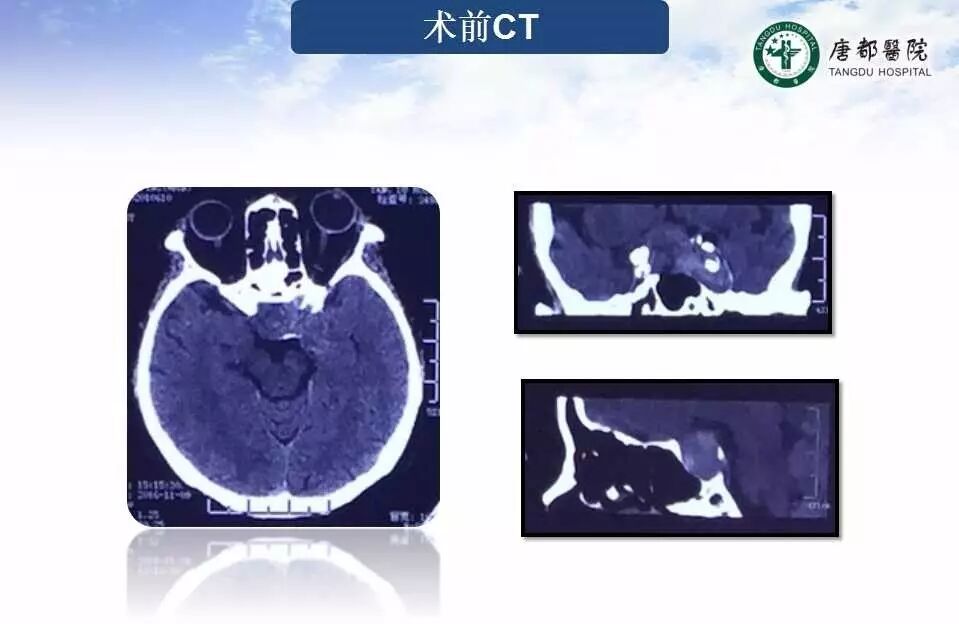

Case 1